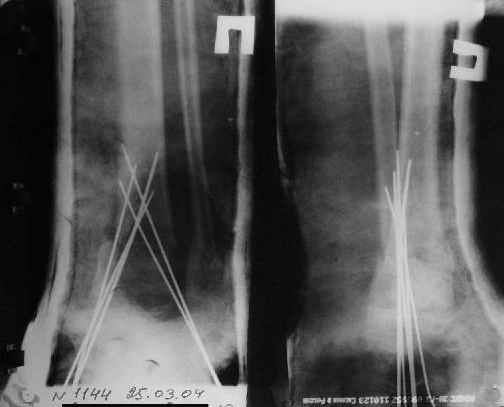

Вытяжение

1) з/репозиция, 2) фиксация 2 спицами, 3) аппарат, 4) фиксационные

спицы удалены...

См. аттачт.